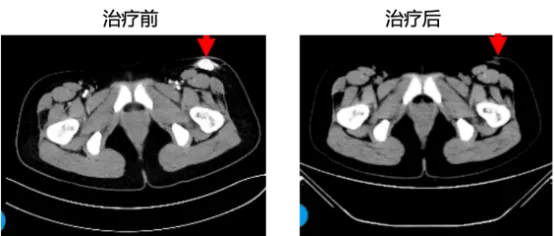

图2:8mg剂量组NTRK融合且既往未接受过TRK抑制剂治疗患者,左大腿梭形细胞肿瘤,TPM3-NTRK1融合,手术切除+化疗后进展,口服ICP-723(8mg)治疗一个周期后,首次肿瘤疗效评估为PR,靶病灶缩小37%,疗效在第二周期治疗后得以确认,目前患者正接受第11周期的治疗,疗效呈维持状态。